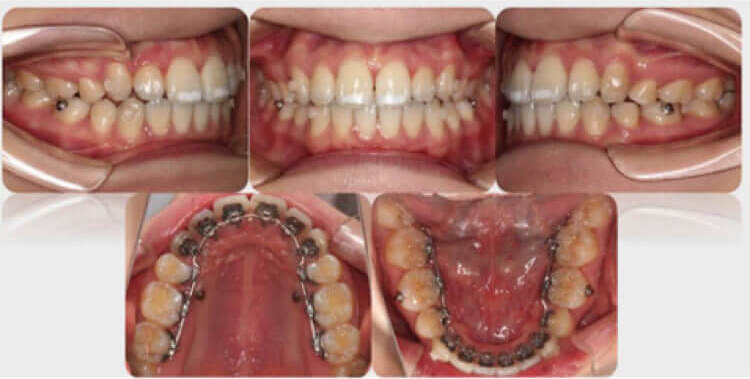

什么是舌侧矫治 舌侧矫治有什么优点和缺点 近年来成人正畸患者明显增加,针对成人患者希望正畸治疗尽量不影响日常工作和生活的特点和要求,一些利于美观的矫治技术应运而生,如:舌侧矫治技术、无托槽矫治技术等。无... 牙齿矫正 admin 666 2023-10-16